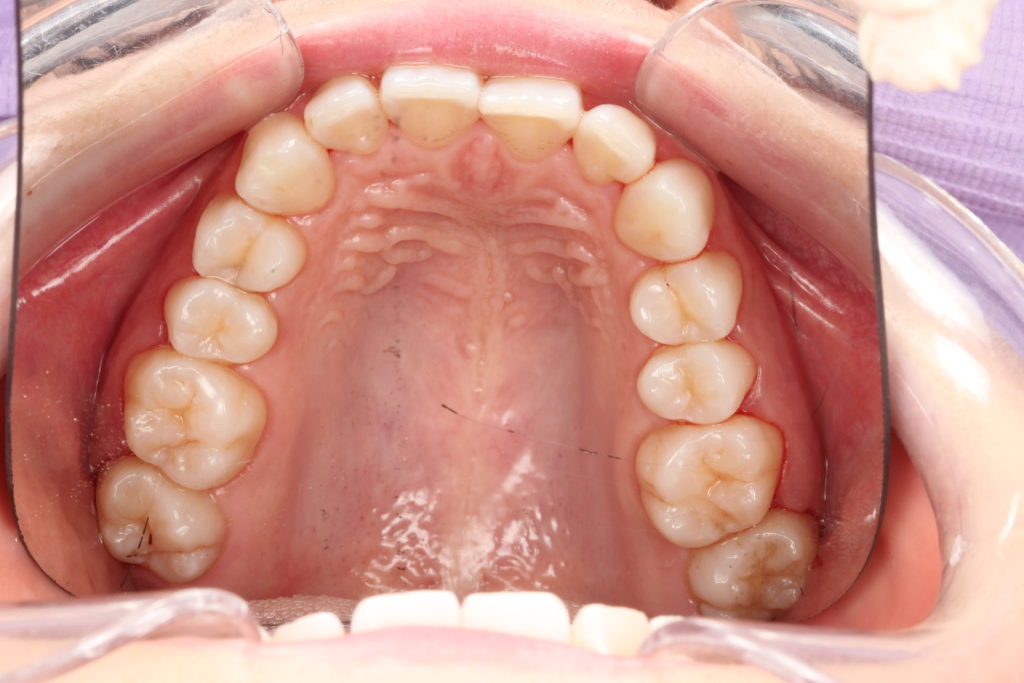

• Analyse dentaire et occlusale : largeur du palais, encombrement, béance, décalages entre mâchoires.

Chez l’enfant présentant un déficit transversal du maxillaire (palais étroit), un appareil d’expansion (ex. disjoncteur palatin, plaque d’expansion) peut être proposé pour élargir progressivement la mâchoire supérieure. En pratique :

• L’expansion vise d’abord à corriger la morphologie (largeur du palais). Des améliorations respiratoires sont possibles lorsque l’étroitesse palatine participait à la gêne nasale, mais elles ne sont ni systématiques ni l’objectif unique du traitement.

Des signes simples peuvent alerter : bouche souvent entrouverte au repos, lèvres sèches, ronflements, sommeil agité, difficultés de concentration, posture de tête en extension, palais étroit ou dents qui manquent de place. Un examen clinique permet d’objectiver le mode respiratoire et d’évaluer les arcades.

Outre l’inconfort (sécheresse, haleine), la respiration buccale peut s’accompagner d’un déséquilibre des forces (langue/lèvres) et d’un palais étroit chez certains enfants ; cela peut majorer un encombrement dentaire ou une béance. Au niveau des gencives, une hygiène difficile et l’assèchement peuvent favoriser une inflammation. Une évaluation précoce permet d’adapter la prise en charge.